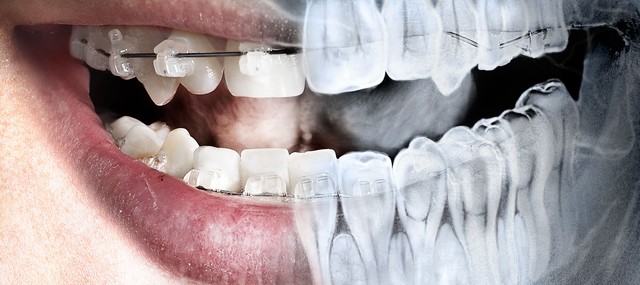

• TÉCNICA DE ALETA MORDIBLE

TÉCNICA DE ALETA MORDIBLE

TÉCNICA DE ALETA MORDIBLE1940.- Roger.- Elabora la Técnica de aleta mordible.